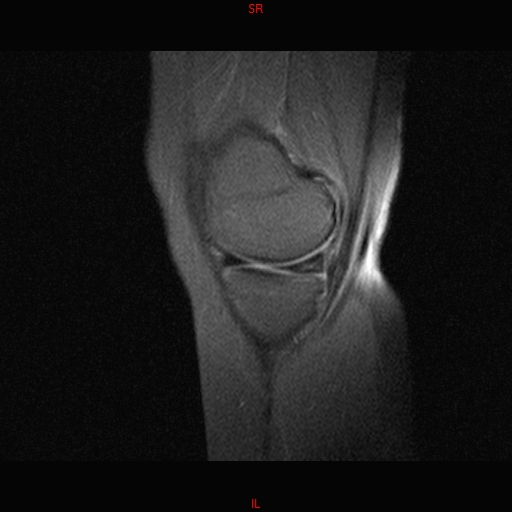

• RESONANCIA PATOLÓGICA MENISCOPATIA INTERNA DP SAGITAL